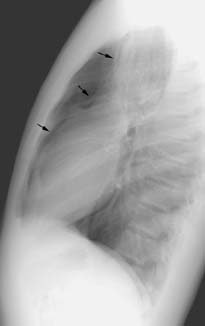

Pneumomediastinum:

The patient shown below presented with chest pain after swimming. Vertically oriented radiolucencies can be seen in the lower neck bilaterally. Vertical lucencies can also be seen anterior to the heart and great vessels within the anterior mediastinum on the lateral view.